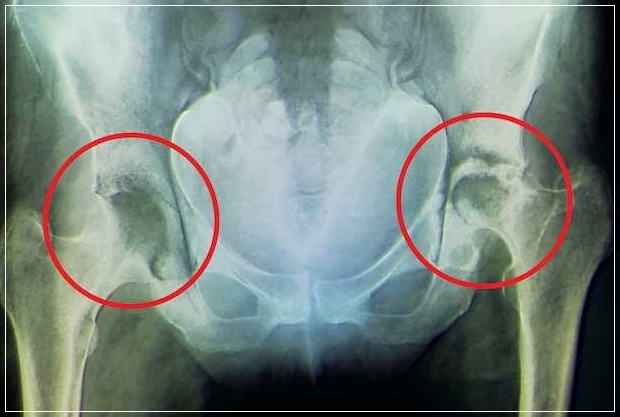

고관절통증은 노화로 인한 퇴행서 질환이라고 생각하는 분들이 만지만 선천적으로 타고난 고관절 모양에 따라 나타날 수 있고 고관절의 무리한 사용으로 무리가 갔을 때 발병하기도 합니다. 고관절 통증은 허리 디스크나 척추 질환, 엉덩이 통증과 비슷한 점이많아 잘 못 오인해 치료 시기를 놓치는 경우가 많습니다.

고관절은 골반과 허벅지 뼈를 이어주는 관절로 엉덩이 관절이라고도 불리며 우리 몸의 상체와 다리를 연결해 주는 대퇴골에 위치해 골반과 넓적다리뼈가 연결되는 관절입니다. 이 부분은 우리 몸을 지탱하며 하반신의 움직임에 결정적인역할을 하는 중요한 신체 부위입니다.

고관절 통증은 대게 나타나지 않다가 병이 상당히 진행된 다음에야 갑자기 시작되는 경우가 대부분이며 발을 땅에 디딜 때 심해져서 절뚝거리며 걷게 되고 양반다리와 같은 특정한 자세를 취할 때 통증을 느끼게됩니다. 엉치 쪽에 통증이 지속하거나사타구니, 무릎위쪽부터 골반 아래쪽까지 통증이 있을 때 보행 중에 통증 때문에 절뚝거리는 등 지장이 생기고 다리가 잘 펴지지 않으면 고관절 질환을 의심해 보아야합니다.

고관절 통증은 통증 자체로 보면 자칫 허리 디스크 질환과 혼동될 수도 있는데 그 이유는 고관절 자체가 다른 부위와는 달리 신체의 깊숙한곳에 있는데다 통증 부위 또한 정확하지 않기 때문입니다. 갑작스럽게 통증이 찾아오기 때문에 대수롭지 않게 여기고 넘겨서 병을 키우는 경우가 많습니다. 특히 이미 퇴행성 진행이 되고 있는 환자의 경우 방치하면 퇴행성 고관절염으로 악화될 수 있습니다.